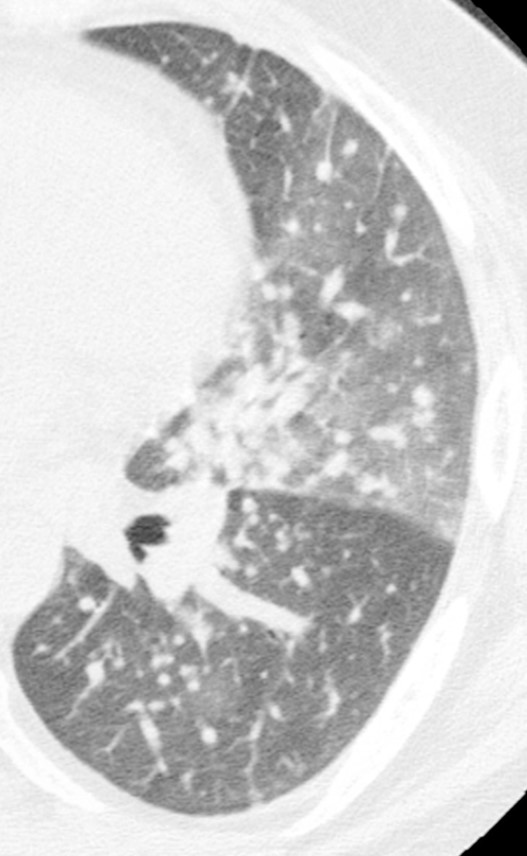

Example

Lacking honeycombing, probable UIP exhibits bronchiectasis and may have histopathologic signs of UIP upon biopsy. Surgical biopsy therefore may aid in IPF diagnosis.3

Note the lack of honeycombing in this image.

HRCT image of possible usual interstitial pneumonia. Reprinted from Fishman‘s Pulmonary Diseases and Disorders. 4th edition 2007. Meltzer EB and Noble PW: Chapter 70, Idiopathic Pulmonary Fibrosis.10 Used with permission from McGraw-Hill Companies. Inc. Copyright © 2007 McGraw-Hill Companies. Inc.